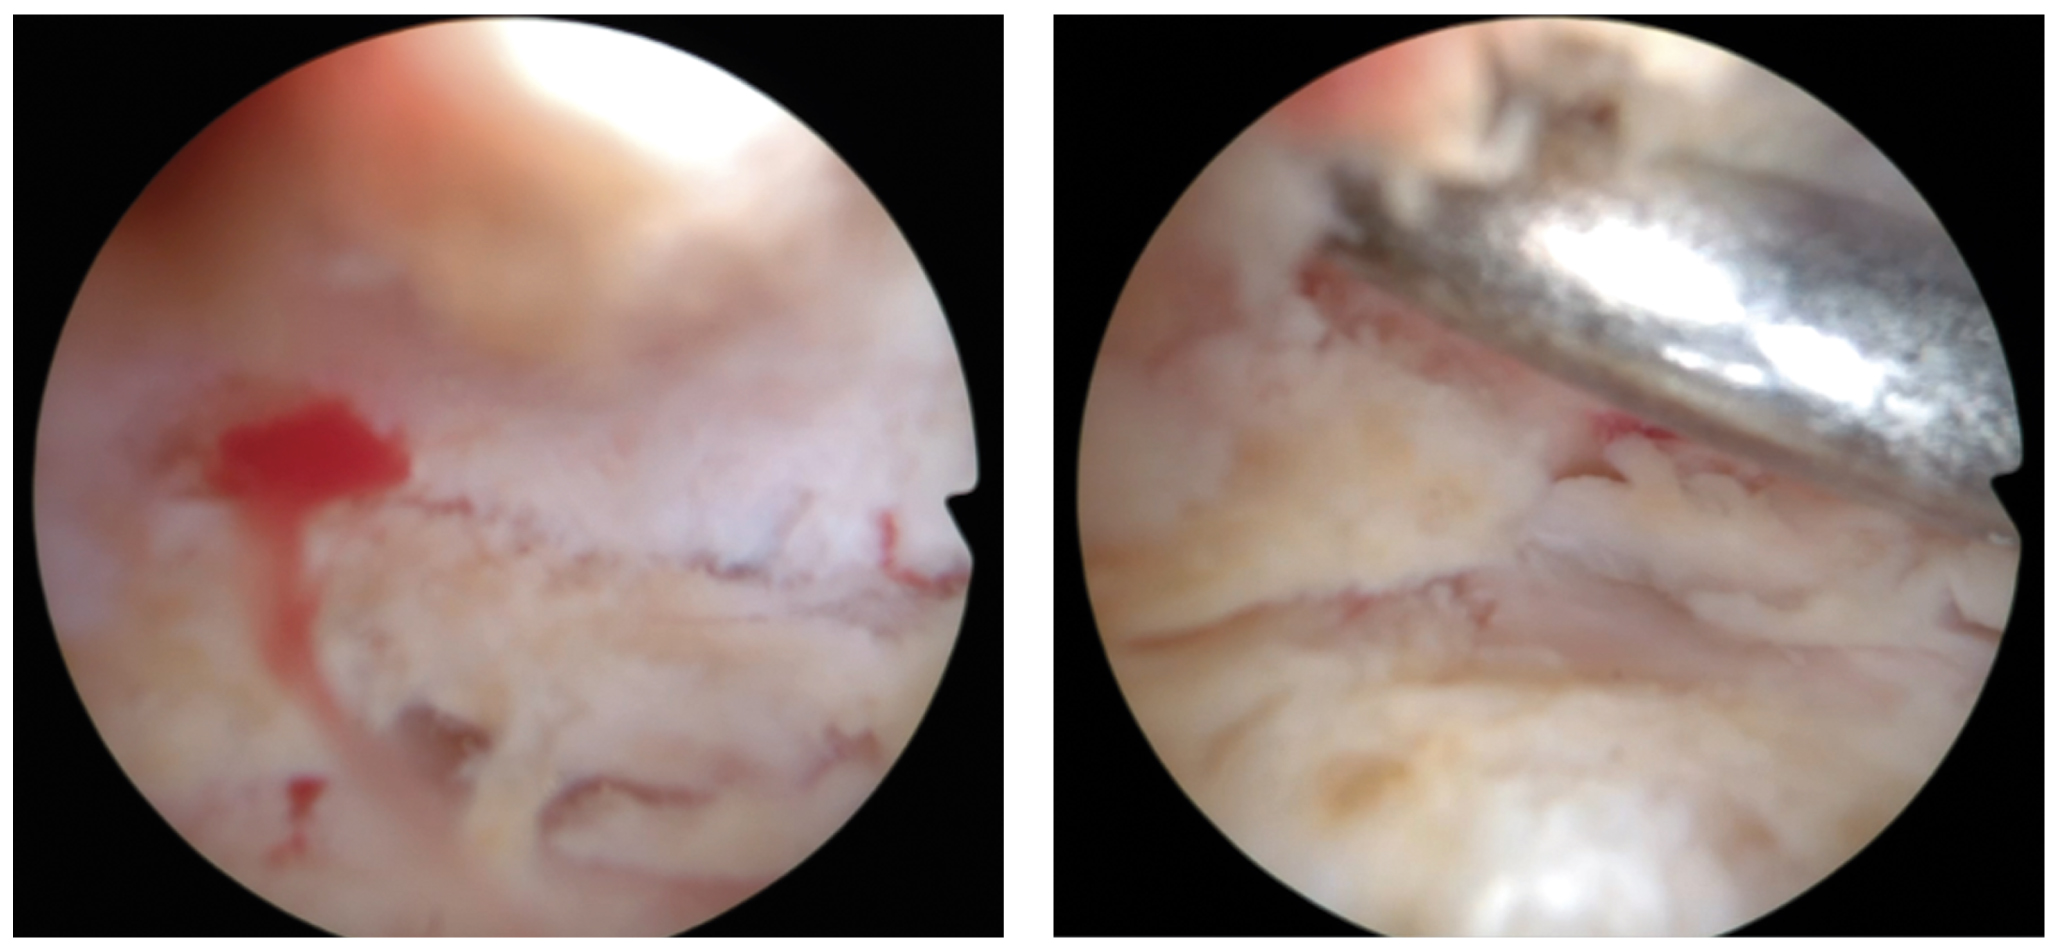

Patient No. 1 before the distraction arthroplasty of the ankle joint had a total absence of cartilage tissue (grade IV according to the Outerbridge scale) (Fig. 3). At the moment of de-installing the Ilizarov frame, repeated arthroscopy was carried out, revealing the presence of abundantly vascularized soft connective tissue, which was completely filling the ankle joint cavity. The arthroscopic signs of arthrofibrosis are provided in Fig. 4.

Fig. 4. Arthroscopic image of total arthrofibrosis of patient No. 1 at the time of removing the Ilizarov frame.

Patient No. 3 previously had signs of arthrofibrosis, which were not detected in 6 months from the moment of the distraction arthroplasty of the ankle joint. The articular fissure is not filled with the connective tissue, which allows for judging on its complete degradation to the end of 6 months of follow-up.